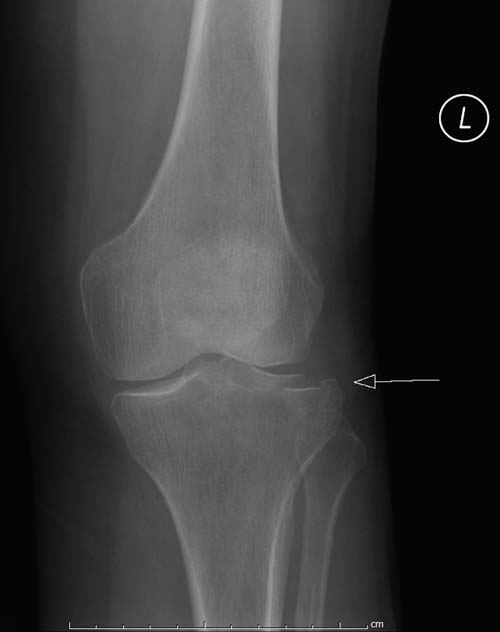

Re: Импрессионный перелом латерального мыщелка левой большеберцевой кости.

оперировать вероятнее всего надо, импрессия приличная , думаю около 1,5 см, только вот она в задних отделах, преимущественно. Если ставить опорную пластину, то делать это нужно сзади, иначе никакой опорности, а задний котртекс по КТ похоже замят

Учитывая, что у пациента молодой возраст(судя по рентгенограммам,абсолютно показано восстановление суставной линии: подменисковый доступ,подъём импренированной части мыщелка, костная аутопластика, остеосинтез, решение вопроса с мениском (шов либо парциальная резекция)).